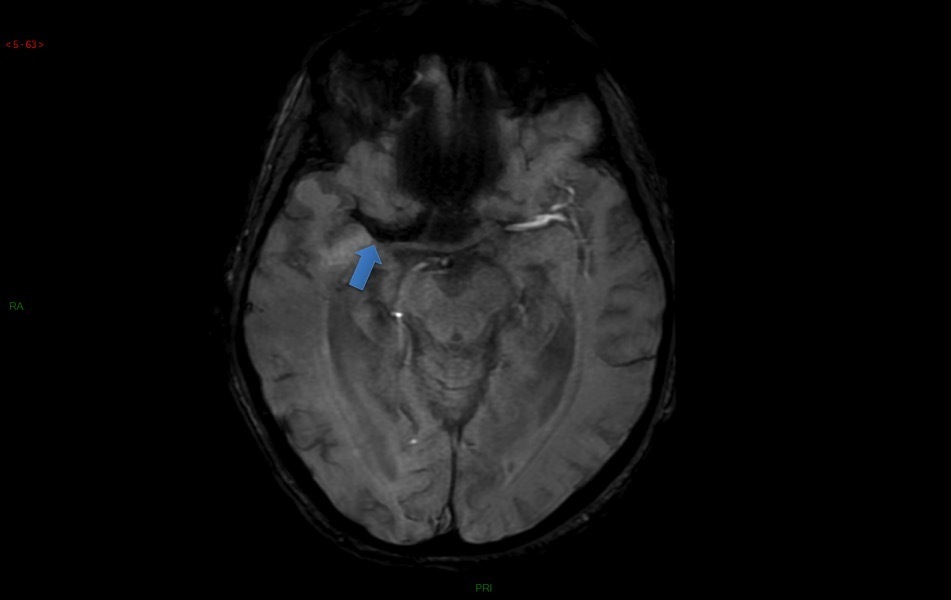

Ci-dessous des coupes axiales Diffusion et Flair de l’IRM cérébrale. La séquence T2* ne présente pas d’anomalie.

Hypersignaux diffusion à la limite de la visibilité en Flair.

L’IRM montre de multiples AVC ischémiques aigus (i. e.  6 heures), corticaux et sous-corticaux, dans des territoires artériels différents.